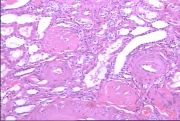

| 2021年12月10日 (五) 13:22 | 24号切片-小叶性肺炎-大体观.jpg (文件) |  |

231 KB | Cirno.9 | 基于MsUpload的文件上传 | 1 |